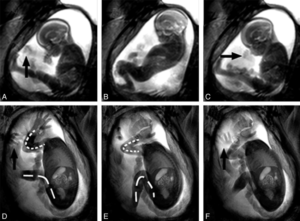

Первые движения будущего ребенка появляются очень рано – их можно увидеть на УЗИ уже с 7 недели, и вместе с сердцебиением они показывают, что плод живой и развивается. А в 12 недель отчетливо видны не просто движения, а ручки-ножки будущего ребенка и то, насколько плод активный – любые нарушения течения беременности приведут или к сниженной, или к чрезмерной двигательной активности.

Свои первые движения плод совершает уже на 8 неделе, но в силу плохого развития нервной системы они хаотичные и мама их не замечает по причине того, что в матке достаточно места. В дальнейшем, когда размеры плода увеличиваются настолько, что он соприкасается со стенками матки, толчки становятся заметными.

Мышечная активность проявляется задолго до формирования нервной системы, скелета и других органов. Уже на 21-й день беременности бьется маленькое сердечко. К началу 9-й недели формируется нервная система, появляются первые рефлексы. На девятой неделе ребеночек заглатывает амниотические воды, что по сути уже довольно сложное движение.

Впервые ребенок начинает двигаться через 8 – 9 недель после того, как появился в организме матери. Если переложить этот срок на акушерские недели, то получится 10 – 11 недель беременности. Сейчас тельце эмбриона «обрастает» тканью, состоящей из нейронов, и пучками мышц.

Работа нервной системы пока еще в зачаточном состоянии, поэтому движения плода не сориентированы в пространстве и похожи на судорожные вздрагивания. Естественно, движения такого крошечного организма внутри женщина пока еще не может ощутить.

Относительно четкую координацию движения плода приобретают к 11 – 15 акушерским неделям беременности, когда у малютки уже есть мозжечок и оба полушария мозга. Благодаря наличию этих важнейших органов ребенок постоянно «егозит» внутри матки, а именно шевелит ножками и ручками, пробует свои пальчики на вкус.